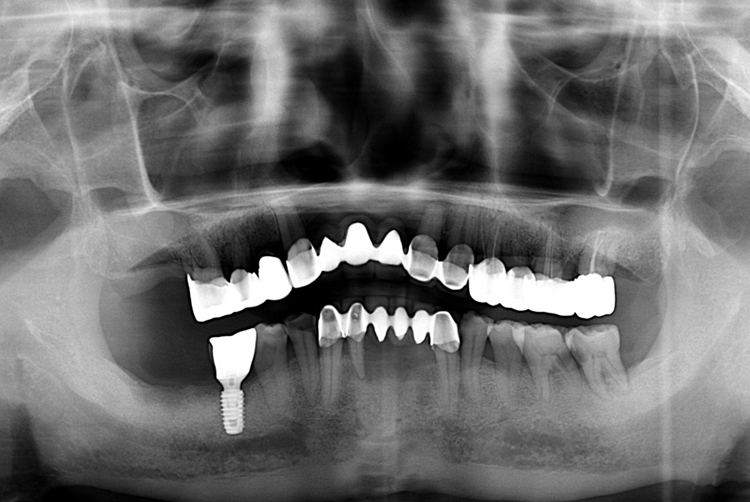

[임플란트] 어금니 임플란트

치료전 : 2016-10-11